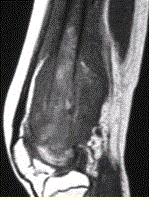

问题 患者男,16岁,左大腿下部疼痛伴肿胀2个月,逐渐加重。自感左膝上方胀痛,尤以夜间为著,伴行走困难。既往史及家族史无特殊。查体:左大腿下部明显肿胀,皮温较对侧升高。碱性磷酸酶明显增高。股骨平片及MRI见下图。 关于此病变的定位,正确的是

选项 A.病变主体位于左股骨下端骨骺,累及干骺端 B.病变主体位于左股骨下端干骺端,累及骨骺 C.病变主体位于左股骨远侧骨端 D.病变主体位于左股骨下端周围软组织,骨质受累 E.病变主体位于骨髓质,皮质受累 F.病变主体位于骨皮质,髓质受累

答案 BE